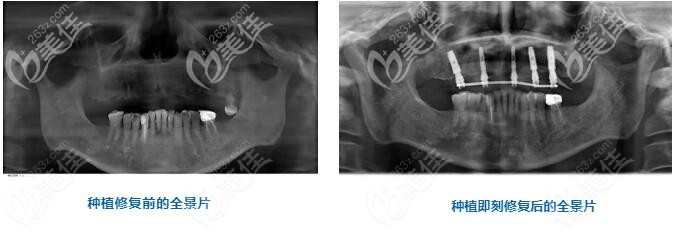

術(shù)后即刻全景片的對(duì)比能直觀的看出來(lái),上半口缺失的牙齒已經(jīng)被種植體所取代。

從秦先生的角度來(lái)說(shuō),半口即刻種植以后都能直接咬甜瓜了,這是他之前所不敢嘗試的。